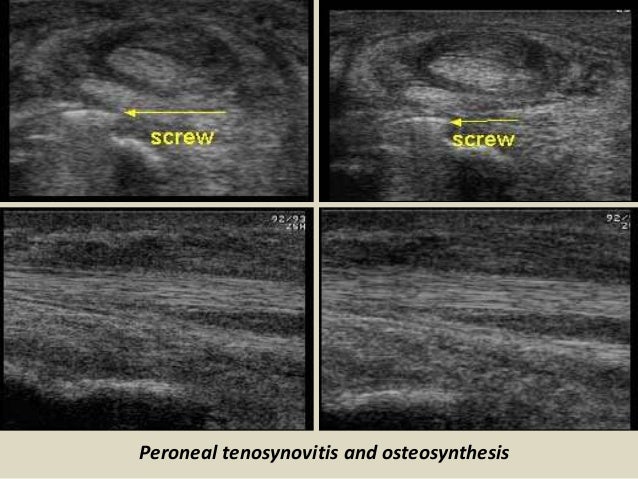

Peroneal tenosynovitis and osteosynthesis

46. 46. Peroneal tenosynovitis and osteosynthesis